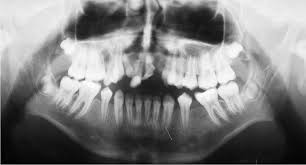

Some form of dental anomalies

Some form of dental anomalies, or at least dental irregularity is found in nearly every individual, including men, women and children. Some of these are relatively mild and simple, as in rotations of teeth, small interdental spacing and unusually shaped teeth. Others are more complex and cause more functional and esthetic concerns. Among the latter, one should include congenitally missing, impacted and severely crowded teeth and also craniofacial anomalies, such as various forms of clefts. An orthodontist, who is primarily concerned with the function and esthetic of the human dentition, sees these dental anomalies as a challenge in his efforts to change a malocclusion to a more normal and cosmetic occlusion.

Traits of Malocclusion

It is well accepted that among all the traits of malocclusions of the modern man, dental crowding is the most preva- lent, possibly second only to the rotation of an individual tooth. For that reason, it is not surprising that dental crowding occupies a central place in this specialty’s discussions about etiology and pathogenesis of malocclusions. It could be well speculated that if practitioners understood the mechanisms of crowding, they could be able, at some point, to intercept or even prevent it and thus substantially reduce the incidence of malocclusion in the modern population. However, the way things stand right now it is not very likely that this important public health issue will be affected any time soon.

Second to dental crowding, anomalies in the number of teeth represent a large group of primary factors causing malocclusions. This is closely followed by an anomalous position of teeth, chiefly represented by impactions and ectopic eruption, but also including transpositions and transmigrations. Therefore, these etiologic factors should also be looked at in an effort to understand and reduce or even eliminate them in the future. Consequently, it is necessary to revisit some of the salient features of these anomalies. Particularly challenging will be to summarize the recent investigative reports in this area, as well as to speculate where future research should be directed. Once we are able to substantially reduce these underlying dental anomalies, we will be well equipped and ready to tackle even more complex cranio-facial problems.

Etiology and pathogenesis of dental crowding

There are two basic mechanisms in creating the condition that we refer to as dental crowding. By definition, crowding is a discrepancy between the cumulative widths of the dental units or teeth, and the available space to accommodate these teeth within the alveolar bone. Thus, one can represent a ratio between the tooth size and the supporting bone size. When this ratio exceeds unity, we define such a condition as dental crowding. If the ratio is one or less than unity, we don’t speak about dental crowding, but may, in fact, identify the condition as dental spacing. Arguably, crowding exceeds spacing by a large margin, perhaps as large as 100 or more to one. The ratio of exact unity or one is so rare in real life that it can, for all practical purposes, be ignored.

It is generally recognized that the most common positional anomaly of a tooth is rotation. Rotations are so prevalent that it is difficult to find a modern man or woman with an occlusion that does not exhibit some degree of this common anomaly. Because this anomaly is so ubiquitous, many clinicians do not even list them as a trait of malocclusion, except when rotations are severe, e.g. a Orthodontics tooth rotated more than 45 degrees.

From the clinical aspect, rotations are not overly difficult to correct, particular- ly with the use of fixed orthodontic appliances. It is important to keep in mind, however, that corrected rotations also represent the condition most likely to relapse. Various strategies have been developed to guard against, or to minimize, rotational relapse. One of the most effective ones is the procedure known as supra-crestal fiberotomy [SCF], a minor surgical procedure in which the supra-crestal gingival fibers are sev- ered.4

Ectopic position constitutes the second most common positional anomaly of the dentition. Within this category, the one that concerns clinicians the most is impaction. Even though any one tooth from either dental arch can be impacted, impaction of the maxillary permanent canine receives most attention. This is the case for numerous reasons, including the central role that the canine plays in the function of articulation and occlusion. A second, nearly equally important reason, is its role in facial esthetics.

A brief mention will be made of yet another positional anomaly of the canines: transmigration. Transmigration is exclusive of the mandibular perma- nent canine. In this anomaly, the canine from one side of the arch migrates through the bone and erupts on the opposite side of the arch. For instance, the right mandibular canine migrates through the sympheseal area and erupts into the arch in the place where the left canine usually erupts. This anomaly could present a complex clinical problem, because the clinician will be facing a situation where the canine from one side appears to be missing, while the opposite side may appear to have a supernumerary canine.15 Like so many dental problems, this last anomaly is best detected by radiographic examination. If detected early enough, its treatment may not be too difficult. This will reinforce the urging of a mature teacher to obtain and examine our patients’ records with care and attention to detail.

A clinician faces a large variety of dental anomalies in his or her everyday work. This review dealt with only the most common ones that particularly affect an orthodontist. A better understanding of these will make the work of a clinician more efficient and perhaps a bit more enjoyable.